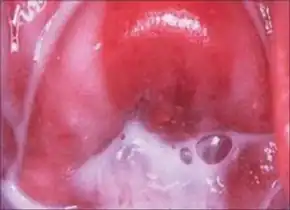

Common symptoms include increased vaginal discharge that usually smells like fish. The discharge is often white or gray in color. There may be burning with urination. Occasionally, there may be no symptoms.[2]

The discharge coats the walls of the vagina, and is usually without significant irritation, pain, or erythema (redness), although mild itching can sometimes occur. By contrast, the normal vaginal discharge will vary in consistency and amount throughout the menstrual cycle and is at its clearest at ovulation—about two weeks before the period starts. Some practitioners claim that BV can be asymptomatic in almost half of affected women,[16] though others argue that this is often a misdiagnosis.[17]

- A characteristic "fishy" odor on wet mount. This test, called the whiff test, is performed by adding a small amount of potassium hydroxide to a microscopic slide containing the vaginal discharge. A characteristic fishy odor is considered a positive whiff test and is suggestive of bacterial vaginosis.